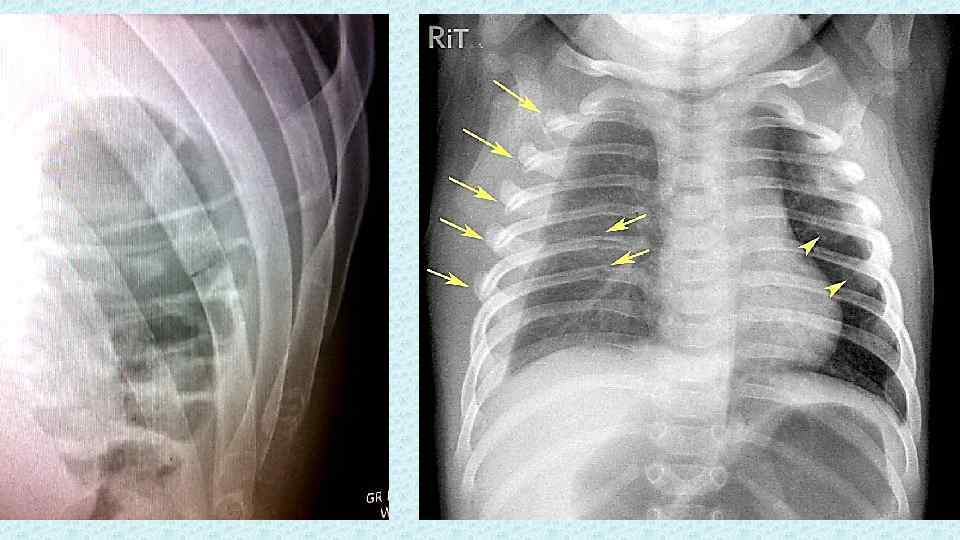

Медицина и диагностика: Аномалии ребер на рентгене